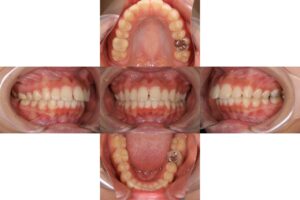

本症例は、出っ歯(上顎前突)に悩まれていた20代女性のケースです。精密検査の結果、上あごが前に出やすい骨格傾向と前歯の強い突出が認められました。さらに、奥歯の一部は神経を取っており、将来的なリスクも考慮する必要がありました。

治療の結果:美しさと健康の共存

治療の結果、前歯の突出感は解消され、口元は自然で美しいラインへと整いました。 特に笑った時の印象がものすごく明るくなり、患者さんからも「自分の歯でここまで変われるなんて」と言われました。最初に書いたように、周りも幸せにできて歯科医師として良い仕事をしたなと思っています。